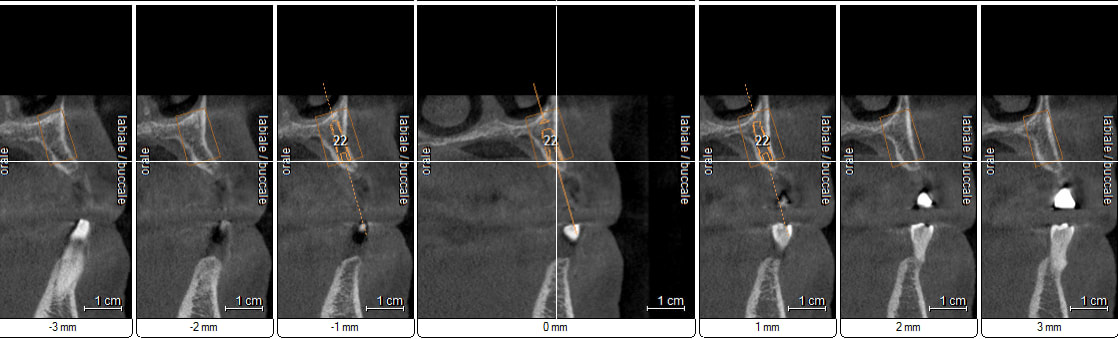

petit cas sympa ancien bridge très mobile....plutôt que d'extraire 25, j'ai déposé la couronne, retraité la dent stabilisation pendant deux mois puis séance d'ostéotension et ce jour pose de deux axioms PX 34120 après expansion...

sinon à la fin t'as combien d'os en vestibulaire et palatin ?

non, uniquement travail par voie crestale, très légère fêlure niveau 23, mais sans conséquence

comme je n'ai pas fait de décharges osseuse en vestibulaire, j'ai effectivement travaillé toute la longueur de la crête, mais, là j'ai ôtè les expanseurs avant de visser les implants car ce sont des PX qui ont un apex assez fin, pour des regular j'aurais pratiqué différemment.

en général (99,9% des cas) je ne constate aucune lyse osseusecrestale, ce type de chir. est très douce pour l'os, lame 15, et ostéotomes, pas de forage, pas de consommation d'os, pas d'agression ni de lavage (piezzo), et je fais toujours attention à laisser du sang (sauf pour les photos) ce qui est le meilleur pansement pour l'os.

par contre les axioms doivent être posé en sous crestal, ce qui est fait ici, avec sans doute comme souvent une nécessitè d’ostéotomie, lors de la mise en charge, car il est fréquent que le col implantaire soit recouvert.

expansion qui donne un résultat correcte je crois